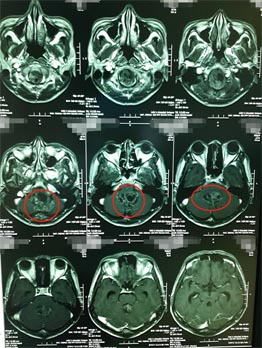

▲术前MR

肿瘤来源于四脑室底,与脑干关系密切。第四脑室是一个非常重要的解剖区域,腹侧毗邻桥脑、延髓等脑干结构,又是脑室系统内脑脊液循环通路的最后环节,由于瘤体周围有重要的神经、血管组织,故手术对肿瘤进行彻底切除难度较大。目前情况下,手术仍是首选的治疗方法。